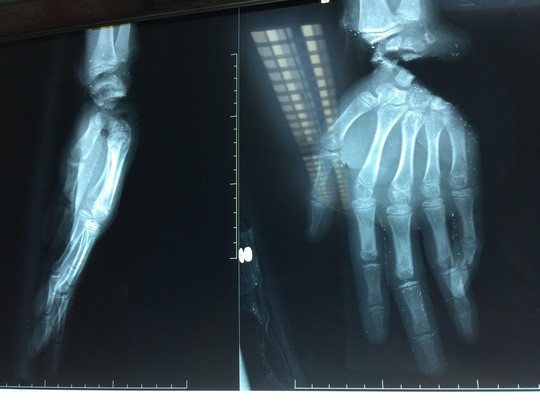

Ngày 14/12, Bệnh viện Chấn thương Chỉnh hình TP. HCM, cho biết vừa cấp cứu thành công cho bệnh nhân Nguyễn Văn Tuấn (14 tuổi, ngụ quận 8, TP.HCM) bị máy sắt cắt gần lìa bàn tay.

Tuấn nhập viện trong tình trạng tái nhợt, lòng bàn tay phải bị đứt sâu, lóc da, bàn tay trái bị đứt lìa khỏi cổ tay. Khi tiếp nhận các bác sĩ đã xử trí cấp cứu các tổn thương, nối lại phần đứt lìa, gân, cơ, mạch máu, thần kinh. Sau 3 giờ 30 phút, bàn tay của Tuấn đã được cứu trước nguy cơ bị hoại tử.

Các bác sĩ cho biết bệnh nhân phải trải qua ca mổ để ghép da cho bàn tay phải sau hai tuần và phẫu thuật để hoàn chỉnh chức năng bàn tay. Để bàn tay được vận động, cầm nắm bình thường, bệnh nhân phải cần tập vật lý trị liệu trong nhiều tháng liền.